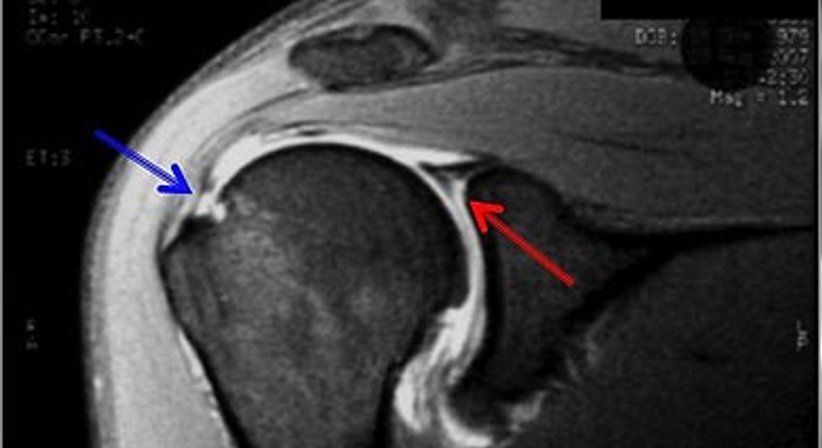

Rotatorenmanschettenruptur

Als Rotatorenmanschette wird jene Muskelgruppe bezeichnet, welche sich zwischen dem Schulterblatt (Scapula) und dem Oberarmkopf (Caput humeri) erstreckt und wie eine Muskelhaube den Großteil des Oberarmkopfes umschließt. Eine intakte Rotatorenmanschette gewährleistet durch das funktionelle Zusammenspiel der einzelnen Muskeln die Hebung bzw. das Abspreizen sowie das Ein- und Auswärtsdrehen des Armes. Weiters trägt die Rotatorenmanschette zur Zentrierung des Oberarmkopfes in der Gelenkspfanne (Glenoid) und somit zur Stabilität des Schultergelenks bei.